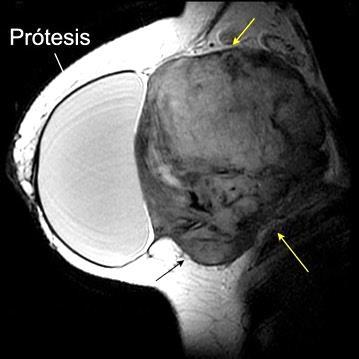

Prótesis

Sombra “simétrica y de densidad “uniforme” de las mamas

Prótesis de ambas mamas densamente calcificadas

Tumor desmoide (“Fibromatosis agresiva”)

T1: Isointensos con músculos.

T2: Señal intermedia y de alta intensidad.

Presencia frecuente de áreas curvilíneas y lineales dentro de la lesión

Mansour J et al. Diagnostic and Imaging Approaches to Chest Wall Lesions. Radiographics 2022